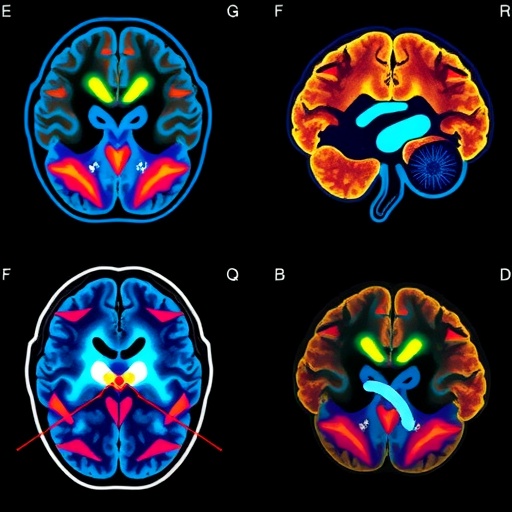

Further molecular analysis demonstrated that the treatment profoundly disrupts mitotic spindle formation during glioblastoma cell division. The mitotic spindle, a cytoskeletal apparatus essential for chromosomal segregation and successful cytokinesis, was found to be frequently malformed or absent in AM RF EMF-treated cells. Such spindle abnormalities were associated with pronounced mitotic arrest, ultimately leading to reduced tumor cell proliferation. Gene expression profiling highlighted alterations in the “Mitotic Roles of Polo-Like Kinase” pathway, a critical cascade regulating spindle assembly and mitotic progression, reinforcing the mechanistic linkage between radiofrequency exposure and mitotic perturbation.

Complementing preclinical evidence, compassionate-use administration of this radiofrequency therapy in two patients with challenging brain tumors provided encouraging clinical signals. A 38-year-old patient with recurrent glioblastoma exhibited both radiographic tumor regression and clinical improvement within a month of treatment initiation. Meanwhile, a 47-year-old patient afflicted with oligodendroglioma tolerated the intervention well, maintaining stable disease as confirmed by serial imaging assessments. Importantly, neither patient experienced serious adverse events, reinforcing the feasibility and safety of this novel treatment approach in a clinical context.